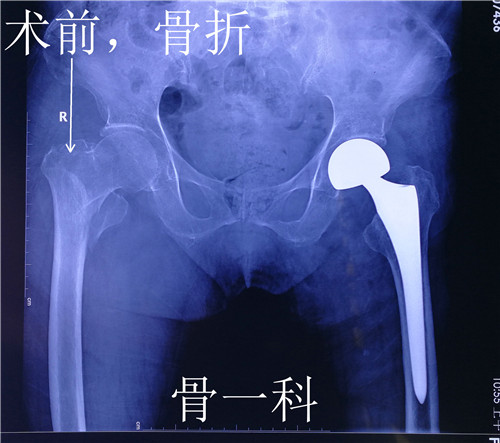

近日,骨一科成功为一位92岁高龄的患者实施了右股骨骨折闭合复位髓内针内固定术,目前患者伤口愈合良好。

据了解,来自渭南市临渭区的郑老太太,年近92岁。9个月前因外伤导致左股骨颈骨折,骨一科为她实施了左侧人工股骨头置换术,术后老人恢复良好,一直在西安女儿家生活。这次老人散步时又不慎摔伤,当即感觉右髋部疼痛,无法站立行走,随后亲属将她送到就近的西安一家医院就诊。在医院拍右髋部x线检查显示,老人右股骨粗隆间骨折粉碎性骨折。该院让她住院手术治疗,她坚决要回渭南在骨一科治疗。

骨一科翁主任和全科医生对老人病情进行了评估和讨论,由于老人是高龄患者,除了右侧股骨粗隆间骨折,之前左侧还做过人工股骨头置换术,并且有骨质疏松症、高血压病、糖尿病Ⅱ型,手术风险和麻醉风险都特别大。在麻醉科李万鹏副主任和徐巧玲主任医师的协助下,骨一科为老人实施了右股骨骨折闭合复位髓内针内固定术,手术非常成功。此手术面对老年髋部股骨粗隆间骨折的特殊人群,优点是减少出血、缩短手术时间、减少创伤、减少麻醉时间,极大降低手术风险。

患者伤口愈合良好